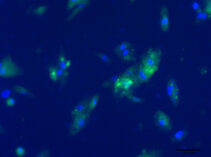

A “core” research team of 2 lab managers is installed at our laboratory to ensure optimal services in developing technical skills of its team members. A variety of standard basic science operations such cell cultures, fluorescence microscopy, Western blot and PCR - just to name some - can be learned at our laboratory.

These images tell a story and we will explain it to you…..